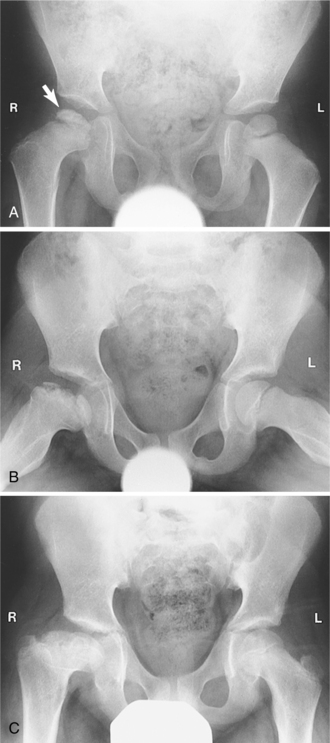

Physical examination, clinical history, and radiographic examination (Fig. 27-28) confirm the diagnosis. MRI is widely accepted as the imaging method of choice, allowing early diagnosis and providing staging information necessary for adequate management.

Figure 27-28 Legg-Calvé-Perthes disease. A, Anterior view of the pelvis demonstrates fragmentation and sclerosis of the right femoral epiphysis (arrow) in a 6-year-old male. B, Follow-up film obtained 8 years later shows continuing deformity resulting from osteonecrosis. C, The child developed significant degenerative arthritis by age 12. (From Mettler FA: Primary care radiology, Philadelphia, 2000, Saunders.)